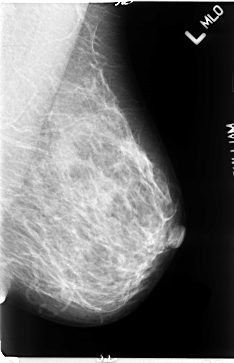

B_3061_1.LEFT_MLO

LEFT_MLO LINES 4712 PIXELS_PER_LINE 3032 BITS_PER_PIXEL 12 RESOLUTION 50 NON_OVERLAY